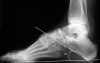

X-ray : 요족(Cavus foot)

편평족과 반대로 아치가 비정상으로 높아진 변형입니다.

후족부에 대하여 전족부가 첨족변형(equinus deformity)을 일으켜 족궁이 비정상적으로 높아집니다.

후족부 내반, 전족부 외번, 중족족지 관절(MTP joint)가 과신전되며, 지간관절은 굴곡되어 갈퀴발가락(claw toe) 변형, 거퇴관절의 배굴 제한을 수반합니다.